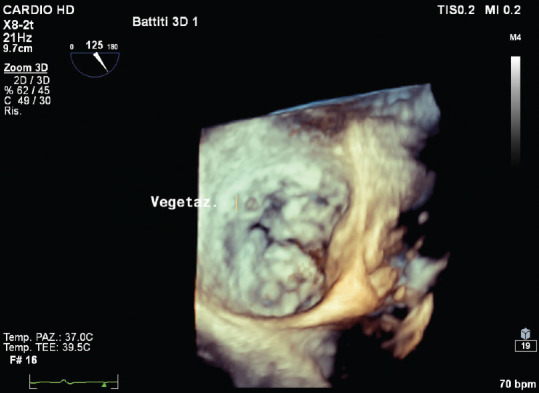

感染性心内膜炎(IE)的诊断基于临床怀疑,并辅以一致的微生物学和仪器数据。心脏瓣膜(原生瓣膜或人工瓣膜)或人工心内膜受累的证据是 IE 的主要诊断标准。经胸超声心动图(TTE)是初步诊断的首选技术,而经食道超声心动图(TEE)则推荐用于 TTE 未确诊或阴性的患者、高度怀疑 IE 的患者以及 TTE 阳性的患者,以记录局部并发症。在对无并发症的 IE 进行随访时,应考虑重复 TTE 和/或 TEE,以检测新的无声并发症并监测植被的大小。在 IE 的情况下,三维(3D)TEE 的作用越来越大;事实上,这种技术也被证明有助于诊断 IE 及其并发症,因为它可以获得无限平面和容积重建。在这篇综述中,我们将介绍三维 TEE 的实用性及其在 IE 治疗中的附加值。

Infective endocarditis (IE) diagnosis is based on a clinical suspicion supported by consistent microbiological and instrumental data. Evidence of involvement of cardiac valves (native or prosthetic) or prosthetic intracardiac material is a major diagnostic criterion of IE. Transthoracic echocardiography (TTE) is the initial technique of choice for the diagnosis while transesophageal echocardiography (TEE) is recommended in patients with an inconclusive or negative TTE, in patients with high suspicion of IE, as well as in patients with a positive TTE, in order to document local complications. Repeating TTE and/or TEE should be considered during follow-up of uncomplicated IE, in order to detect new silent complications and monitor vegetation size. In the setting of IE, the role of three-dimensional (3D) TEE is increasing; in fact, this technique has also been shown to be useful for the diagnosis of IE and its complications as it allows to obtain infinite planes and volumetric reconstructions. In this review, we will describe the usefulness of 3D-TEE and its added value in the management of IE.